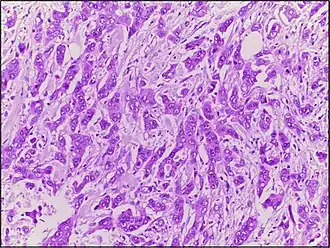

Carcinome canalaire

Les carcinomes canalaires sont une classe de tumeurs solides de la Classification internationale des maladies oncologiques. Elles sont développées aux dépens des canaux excréteurs d'une glande exocrine : sein, pancréas, prostate, glandes lacrymales...